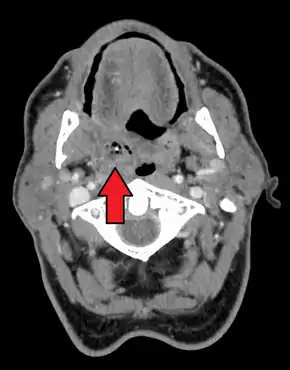

يعتمد التشخيص عادةً على الأعراض.[1] قد يتم اخذ بعض الصور الطبية لاستبعاد اي مضاعفات.[1] الصور الطبية تتضمن تصوير مقطعي، تصوير بالرنين المغناطيسي، أو التصوير بالموجات الفوق الصوتية قد يساعد أيضاً في التشخيص.[1]